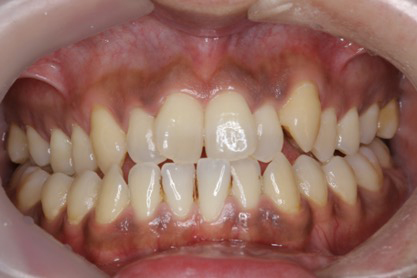

■症例2

Before

After